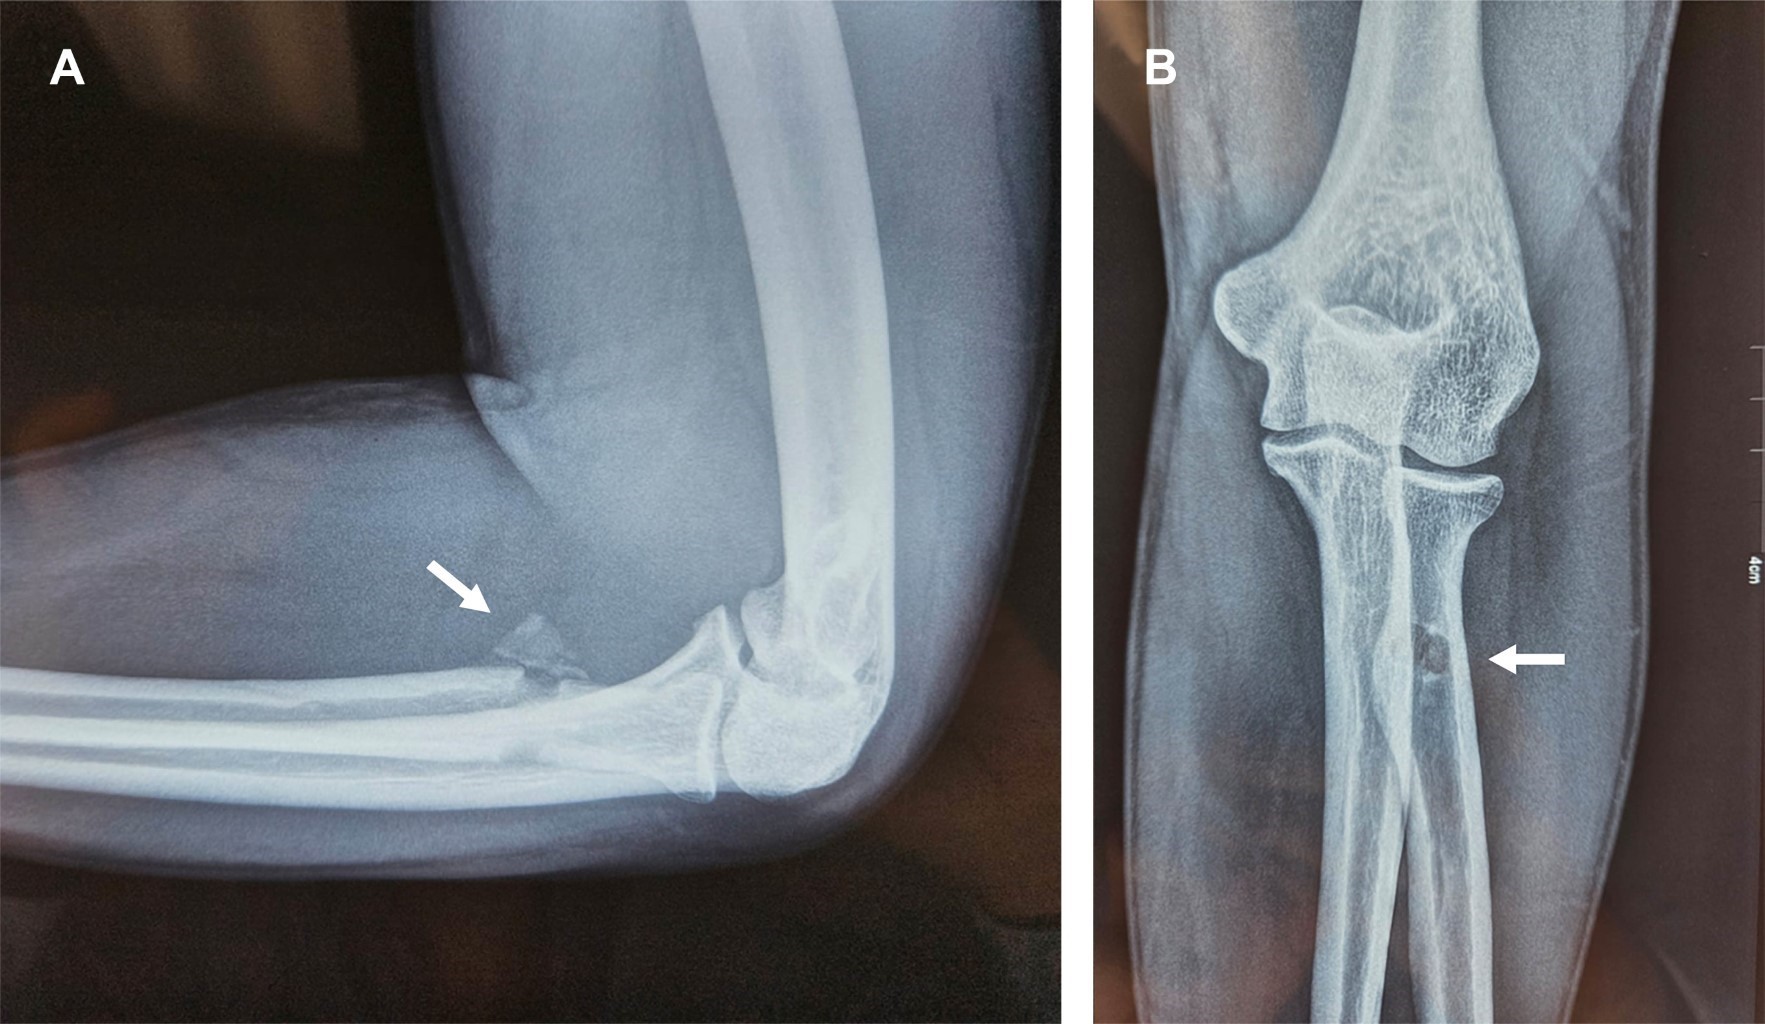

Avulsion fracture of the distal tendon of the biceps brachii (TDB) is rare, with an incidence of 5.35 per 100,000/year. It is observed in athletes performing a forced eccentric brachial biceps contraction. The injuries are evaluated with the "hook test". Tendon repair is performed in acute injuries involving > 50%. Usually, reinsertion through an incision is performed by fixation to the second cortex with a "button" type device. There is no consensus on the best repair method; surgical complications are heterotopic ossification, rigidity, external cutaneous neuropraxia of the antebrachial nerve, and injury to the posterior interosseous branch of the radial nerve.

Figure 2